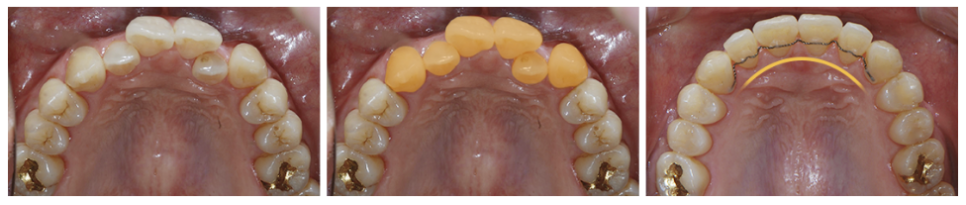

치열이 고르지 못하고 삐뚤빼뚤한

전치부와 송곳니까지

교정을 원하는 치아를 선택하여

치아 라인뿐 아니라 악궁 라인까지

빠르게 개선이 가능합니다.